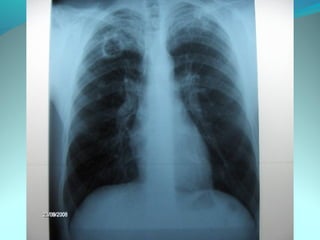

Image radiologique bilaterale

A droite : clarté sous claviculaire et axilaire droite arrondie de 3 cm de

diam entourée d une paroi de 4mm d’épaisseur

Le 1/3 sup du poumon droit est le siege d’opacité nodulaire avec

quelque clarté

A gauche: le 1/3 moyen est le siege d’opacité nodulaire et de clarté de

taille variable

DIAGNOSTIC:

Tuberculose pulmonaire bilaterale cavitaire